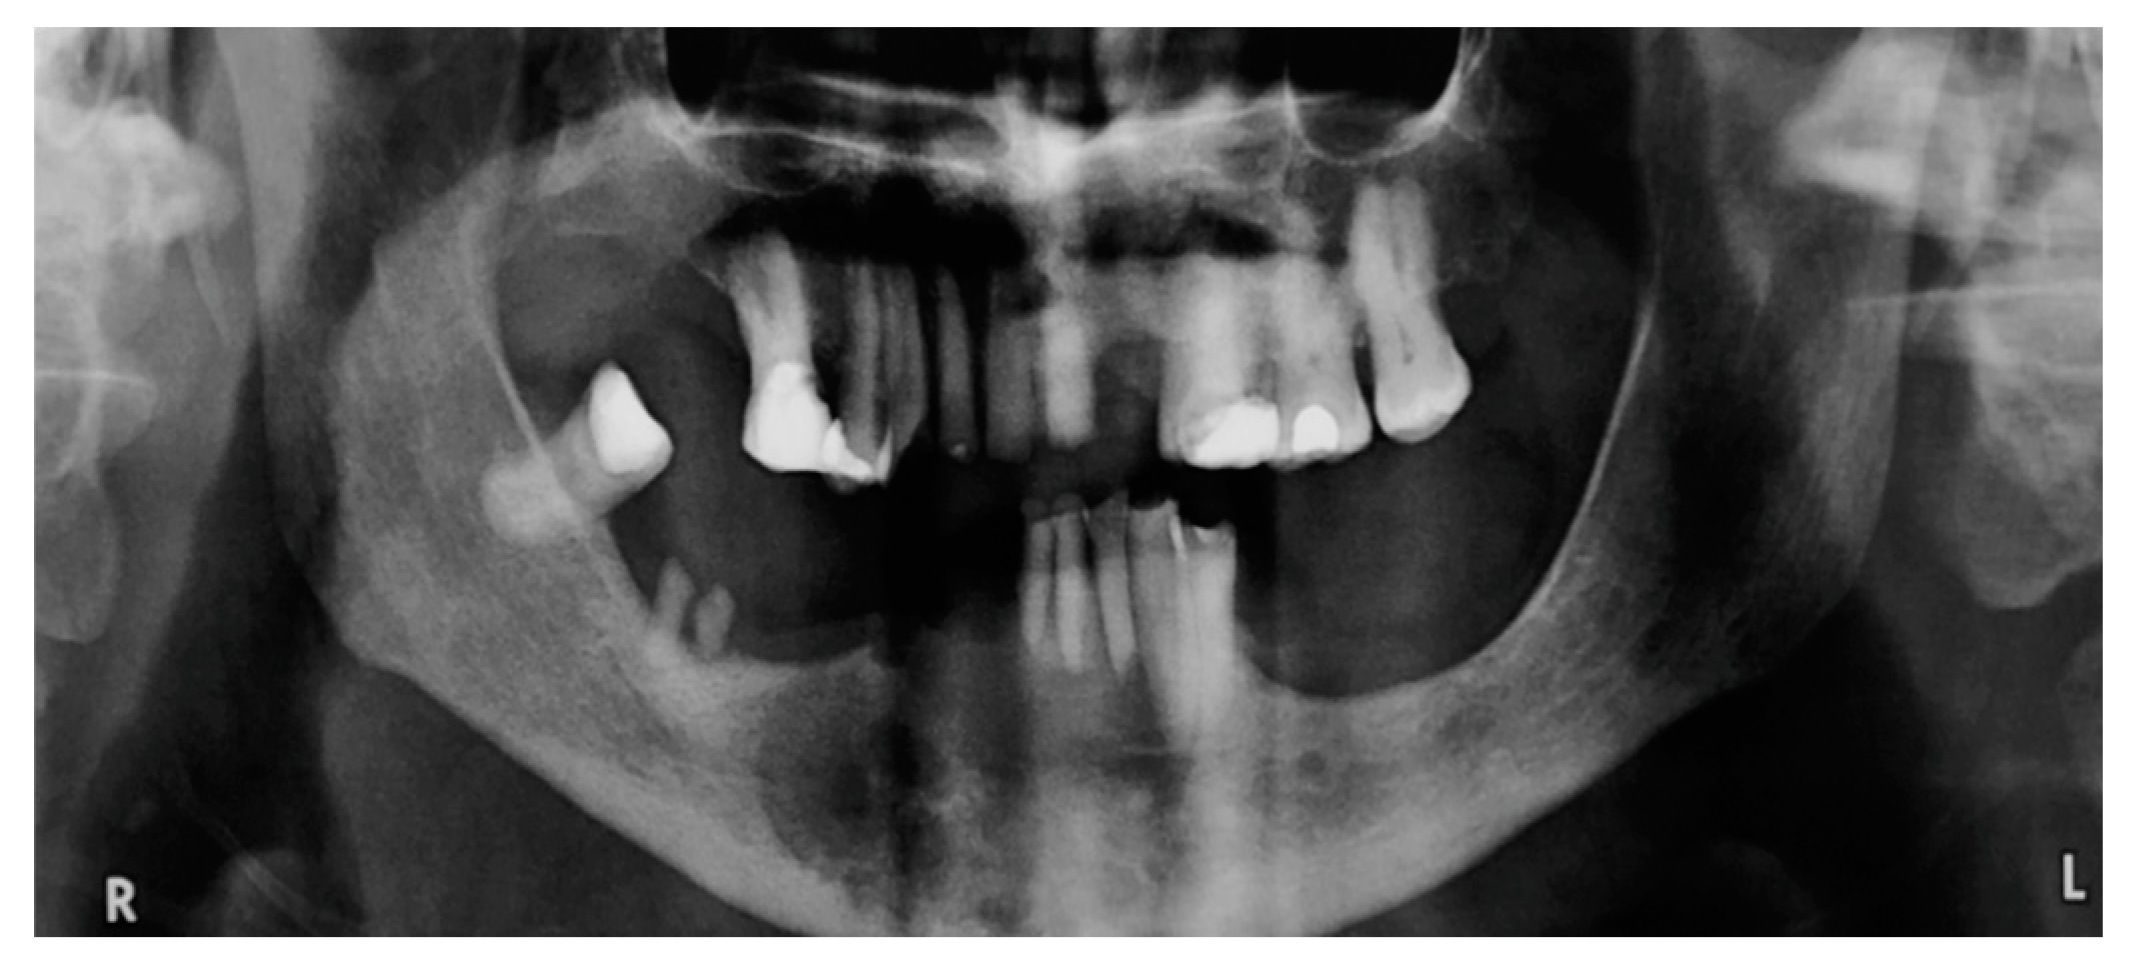

Clear Cell Odontogenic Carcinoma of the Mandible: A Case Report †

2. Case Presentation